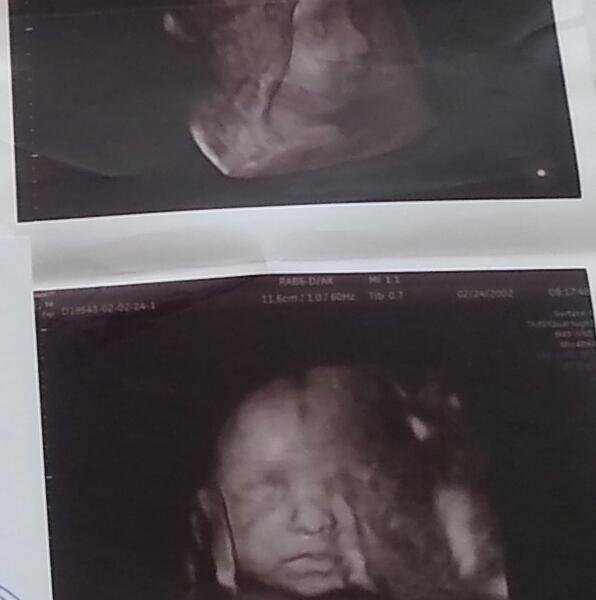

наш малыш ♥ не переться следующего узи чтоб увидеть его:-D

😻😻😻 с ума сойти, уже отчетливо моська видна. Тьфу тьфу)) мне одной кажется, что все дети на УЗИ похожи на моего мужа?😹😹😹 даже этот малыш мне кажется похожим на моего мужа) они масенькие видимо все на одно лицо)

@iraeva, это 4д получается ? ИншаАллагь в след раз сделаю

мне кажется что это копия мужа:-D